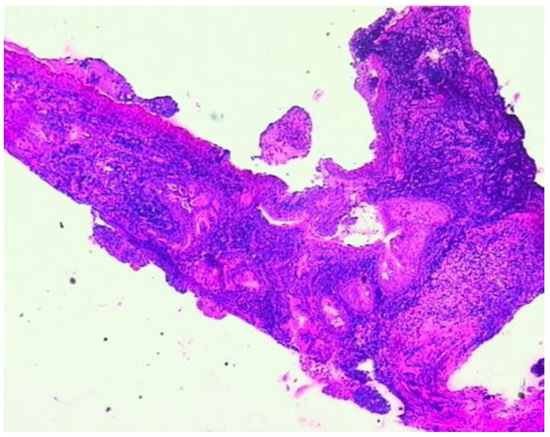

3.2.2. Additional Imaging Assessments

3.2.4. Minimally Invasive Surgery